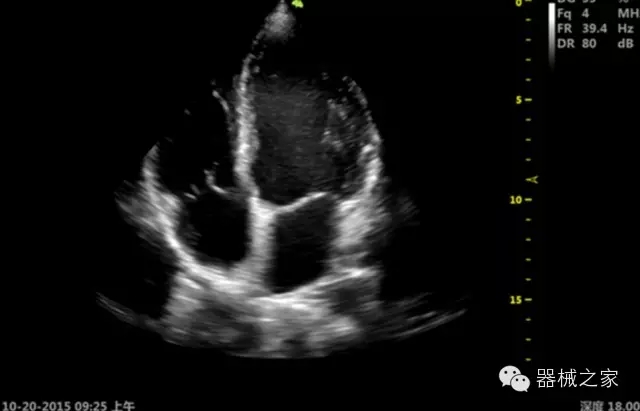

品牌:開立(SONOSCAPE)

深圳開立生物醫(yī)療科技股份有限公司作為中國(guó)民族醫(yī)療產(chǎn)業(yè)的優(yōu)秀引導(dǎo)者,自成立伊始,一直致力于臨床醫(yī)療設(shè)備的研發(fā)和制造,產(chǎn)品涵蓋醫(yī)用數(shù)字超聲診斷系統(tǒng)、電子內(nèi)窺鏡系統(tǒng)、全自動(dòng)五分類血液細(xì)胞分析儀以及自主研發(fā)的探頭群。

經(jīng)典產(chǎn)品:S8EXP

臨床圖片賞析